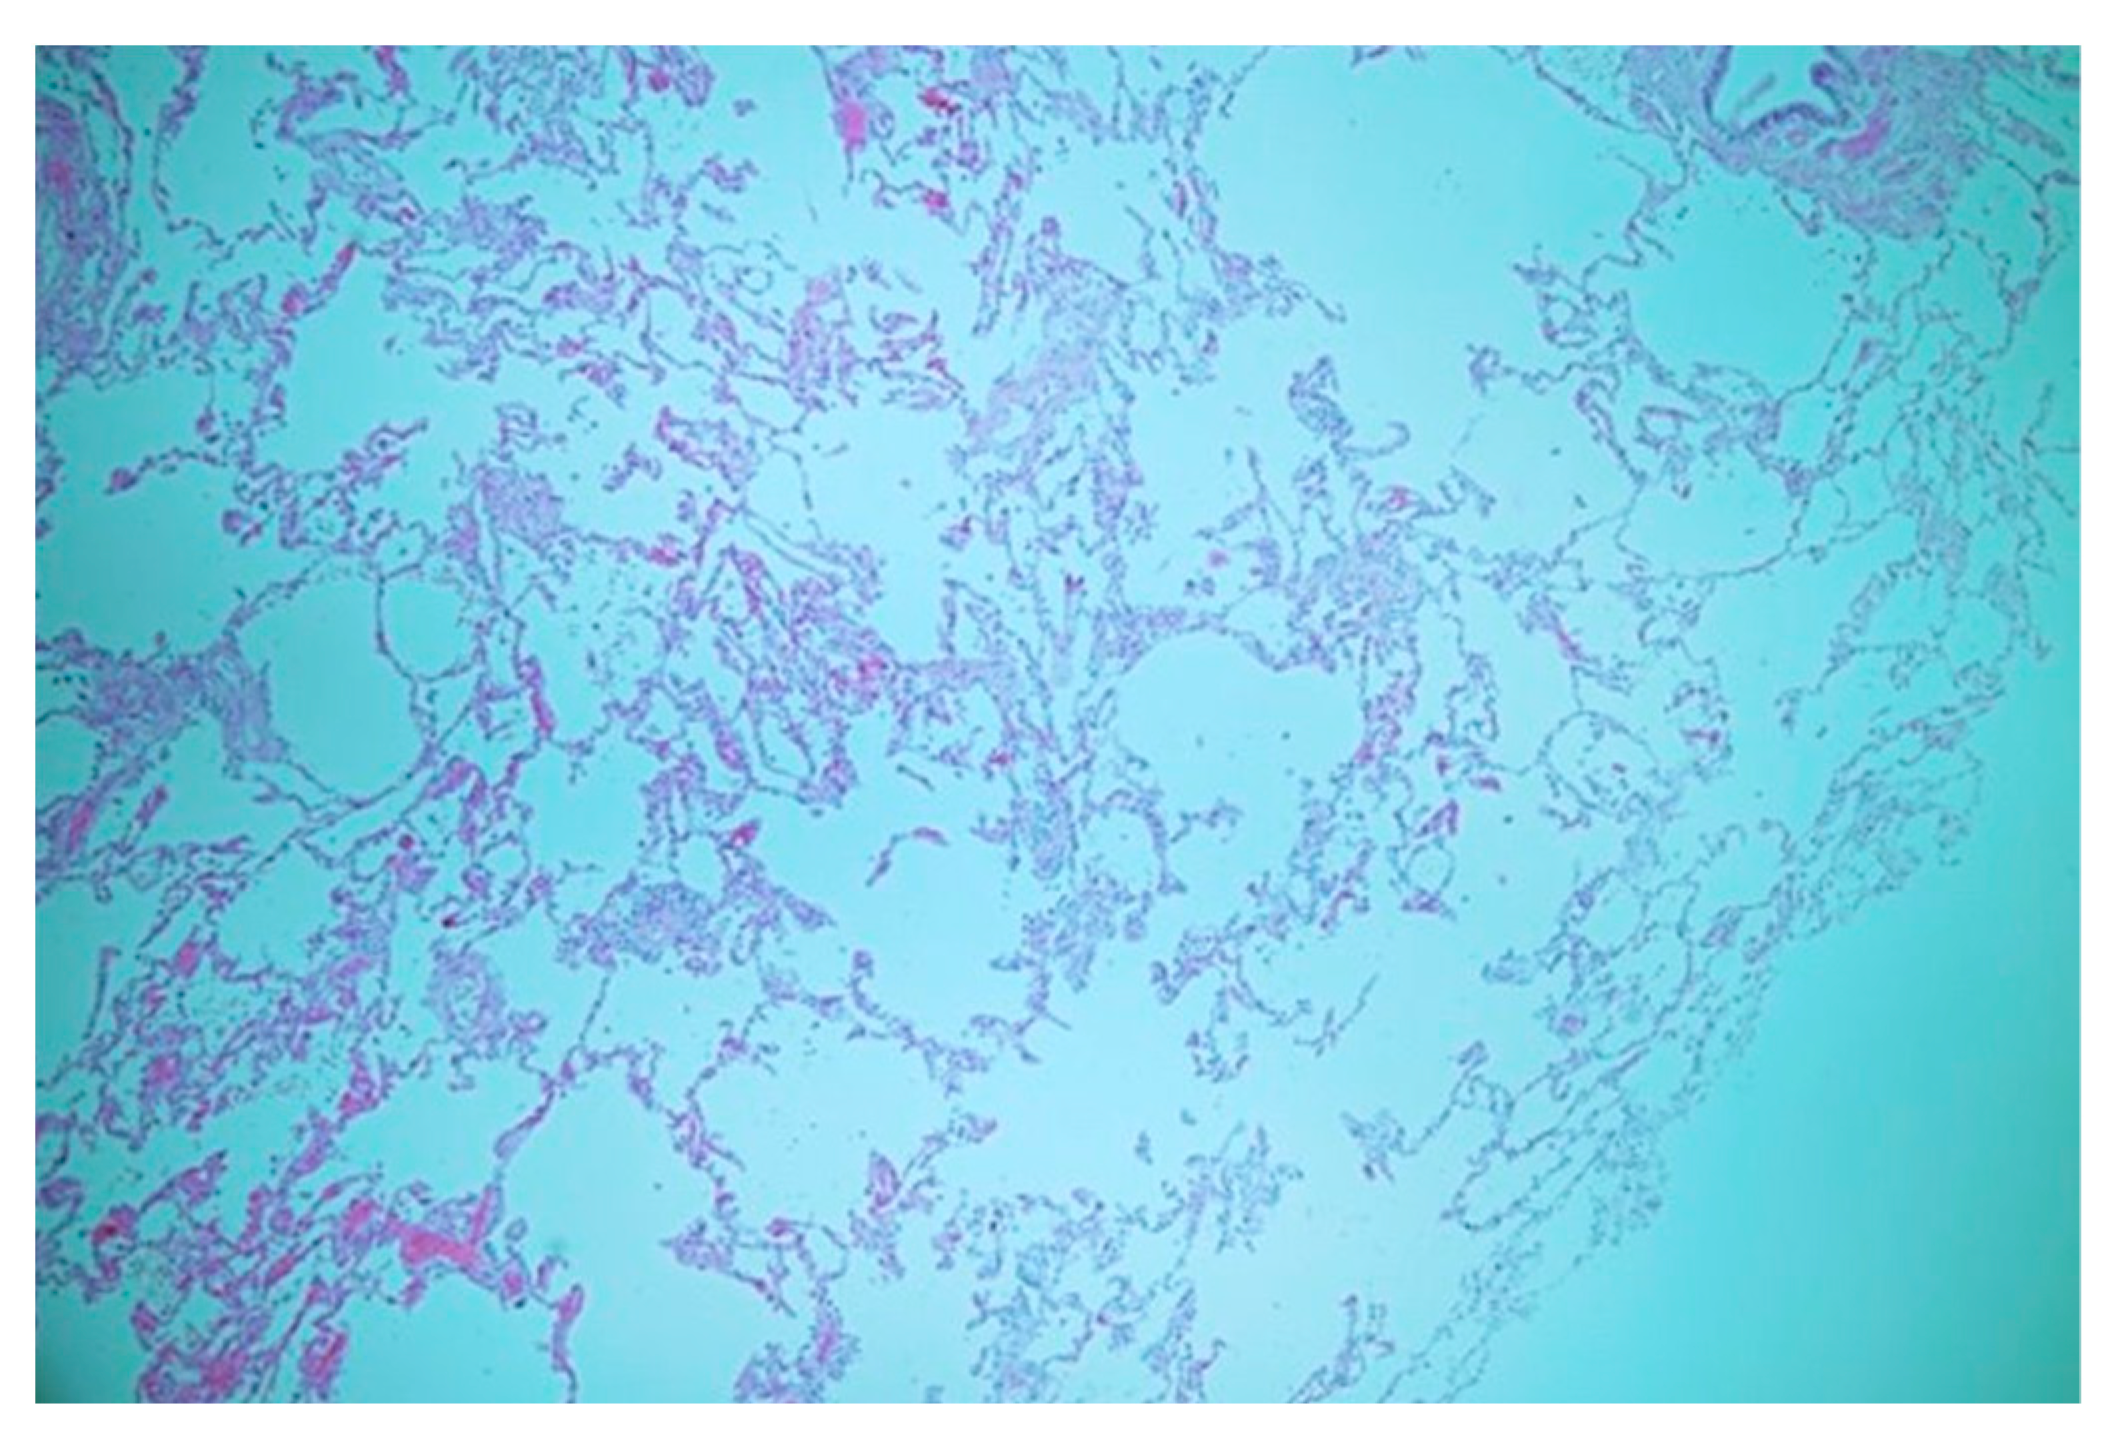

The patient underwent a lobectomy along with feeding artery ligation using an endocutter device (Echelon Flex Power Plus Cutter 60 mm, Ethicon, Cincinnati, OH, USA). Pathological examination revealed the presence of a systemic feeding vessel without notable thickening or atherosclerotic changes (Figure 3). The alveoli exhibited well-developed structures with nonspecific enlargement (Figure 4), appearing clean without inflammatory alterations or mucostasis. Lymph node examination revealed lymphoid hyperplasia, with no pathological evidence of aortopulmonary fistula. The patient did not exhibit any complications upon discharge or at the 3-month follow-up.

Figure 4.

Well-developed alveoli with nonspecific enlargement; the alveolar spaces appeared clean, devoid of any inflammatory alterations, and without mucostasis.